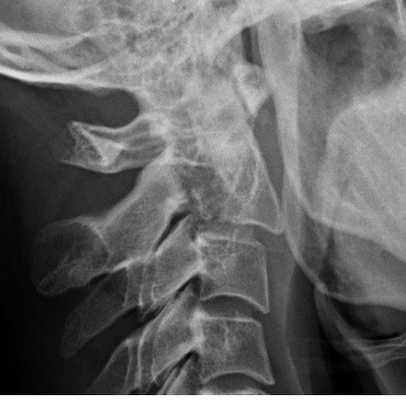

Рентгенограмма. Подвывих в шейном отделе позвоночника. Цветовая обработка изображения.

Половина всех случаев переломов позвоночника приходится на шейный отдел. Многие травмы шейного отдела позвоночника угрожают жизни пациента для жизни пациента. Поэтому они требуют неотложных мероприятий.